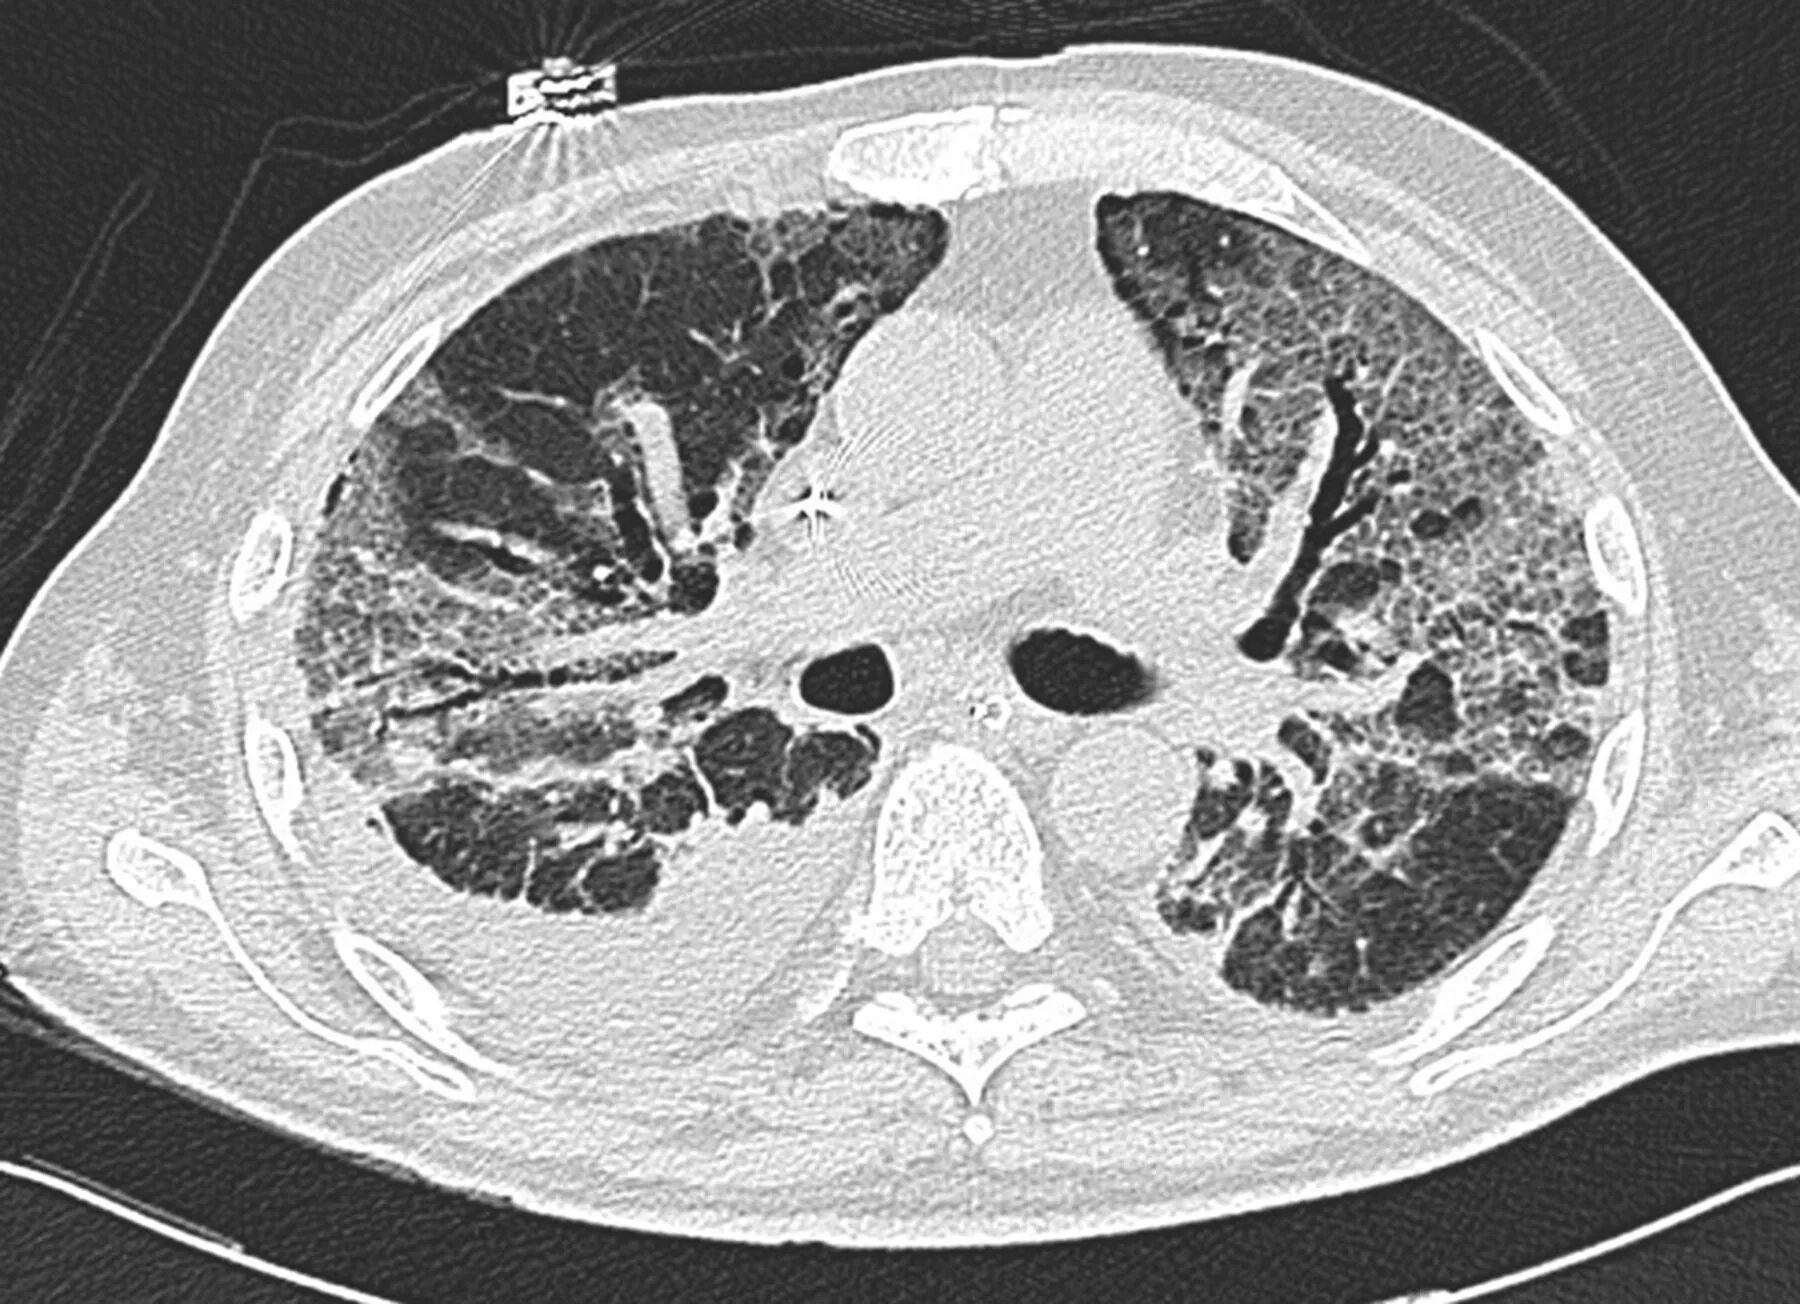

Ордс крипта